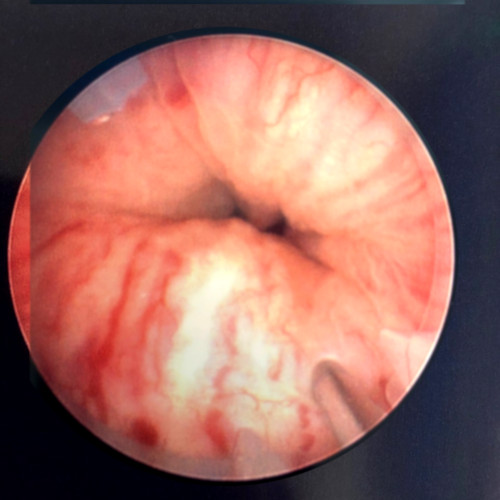

Femme de 65 ans, échec de bandelette sous urétrale trans-obturatrice. Pas de prolapsus génital. Fuites en jets à la toux. Pression de clôture urétrale abaissée à 25 cmH2O, Valsalva leak Point positif avec des poussées de 30 cm H2O. Probable insuffisance sphinctérienne intrinsèque. Avant et pendant l’injection, on observe le bombement de la muqueuse sous l’effet du comblement. Le geste n’est pas très compliqué mais nécessite quand même un peu de dextérité et comme d’habitude, l’expérience améliore les résultats.